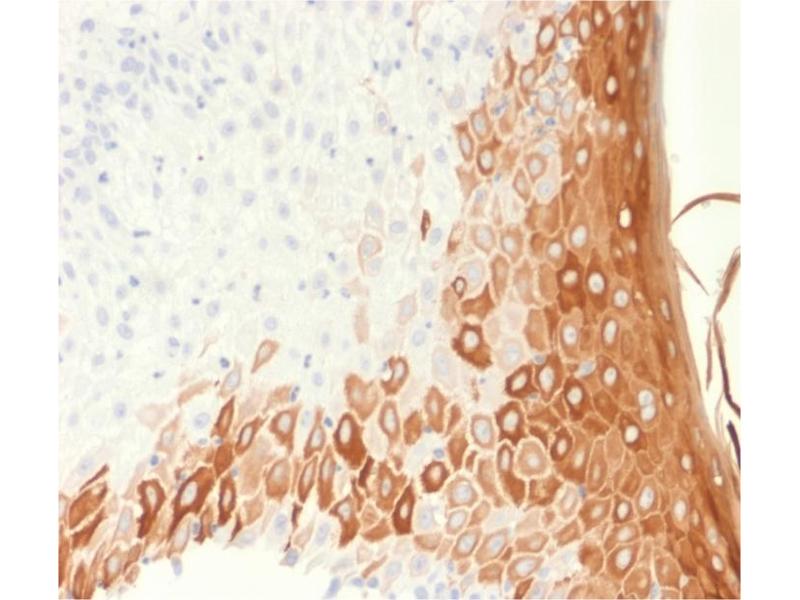

Der Maus Monoklonal anti-Keratin 10 Antikörper (Klon rKRT10-1275) (ABIN6939901) detektiert spezifisch Keratin 10 in IHC und StM. Dieser Antikörper reagiert spezifisch mit Proben aus Human, Hund und Cat.

• Spezifität

This MAb recognizes a protein of 56.5 kDa, identified as cytokeratin 10 (CK10). CK10 is expressed in all suprabasal layers of the epidermis. In the epidermis, expression of CK10 strictly parallels the extent of differentiation, it is absent in the basal layer, appears in the first suprabasal layers and increases in concentration towards the granular layer. However, CK10 is rarely detected in early stages of vulvar squamous carcinomas (tumors less than 2 cm, clinical stage I) regardless of the tumor grade. In larger and more advanced tumors (greater than 2 cm, clinical stages II and III), CK10 is detected very frequently. Expression of CK10 is related to maturation of malignant keratinocytes, being preferentially detected in more-differentiated parts.

Positive Control: A431, HeLa, MCF7 cells. Esophagus or tonsil.

Known Application: Immunohistochemistry (Formalin-fixed) (0.1-0.2 μg/mL for 30 min at RT)(Staining of formalin-fixed tissues requires boiling tissue sections in 10 mM citrate buffer, pH 6.0, for 10-20 min followed by cooling at RT for 20 minutes)Optimal dilution for a specific application should be determined.